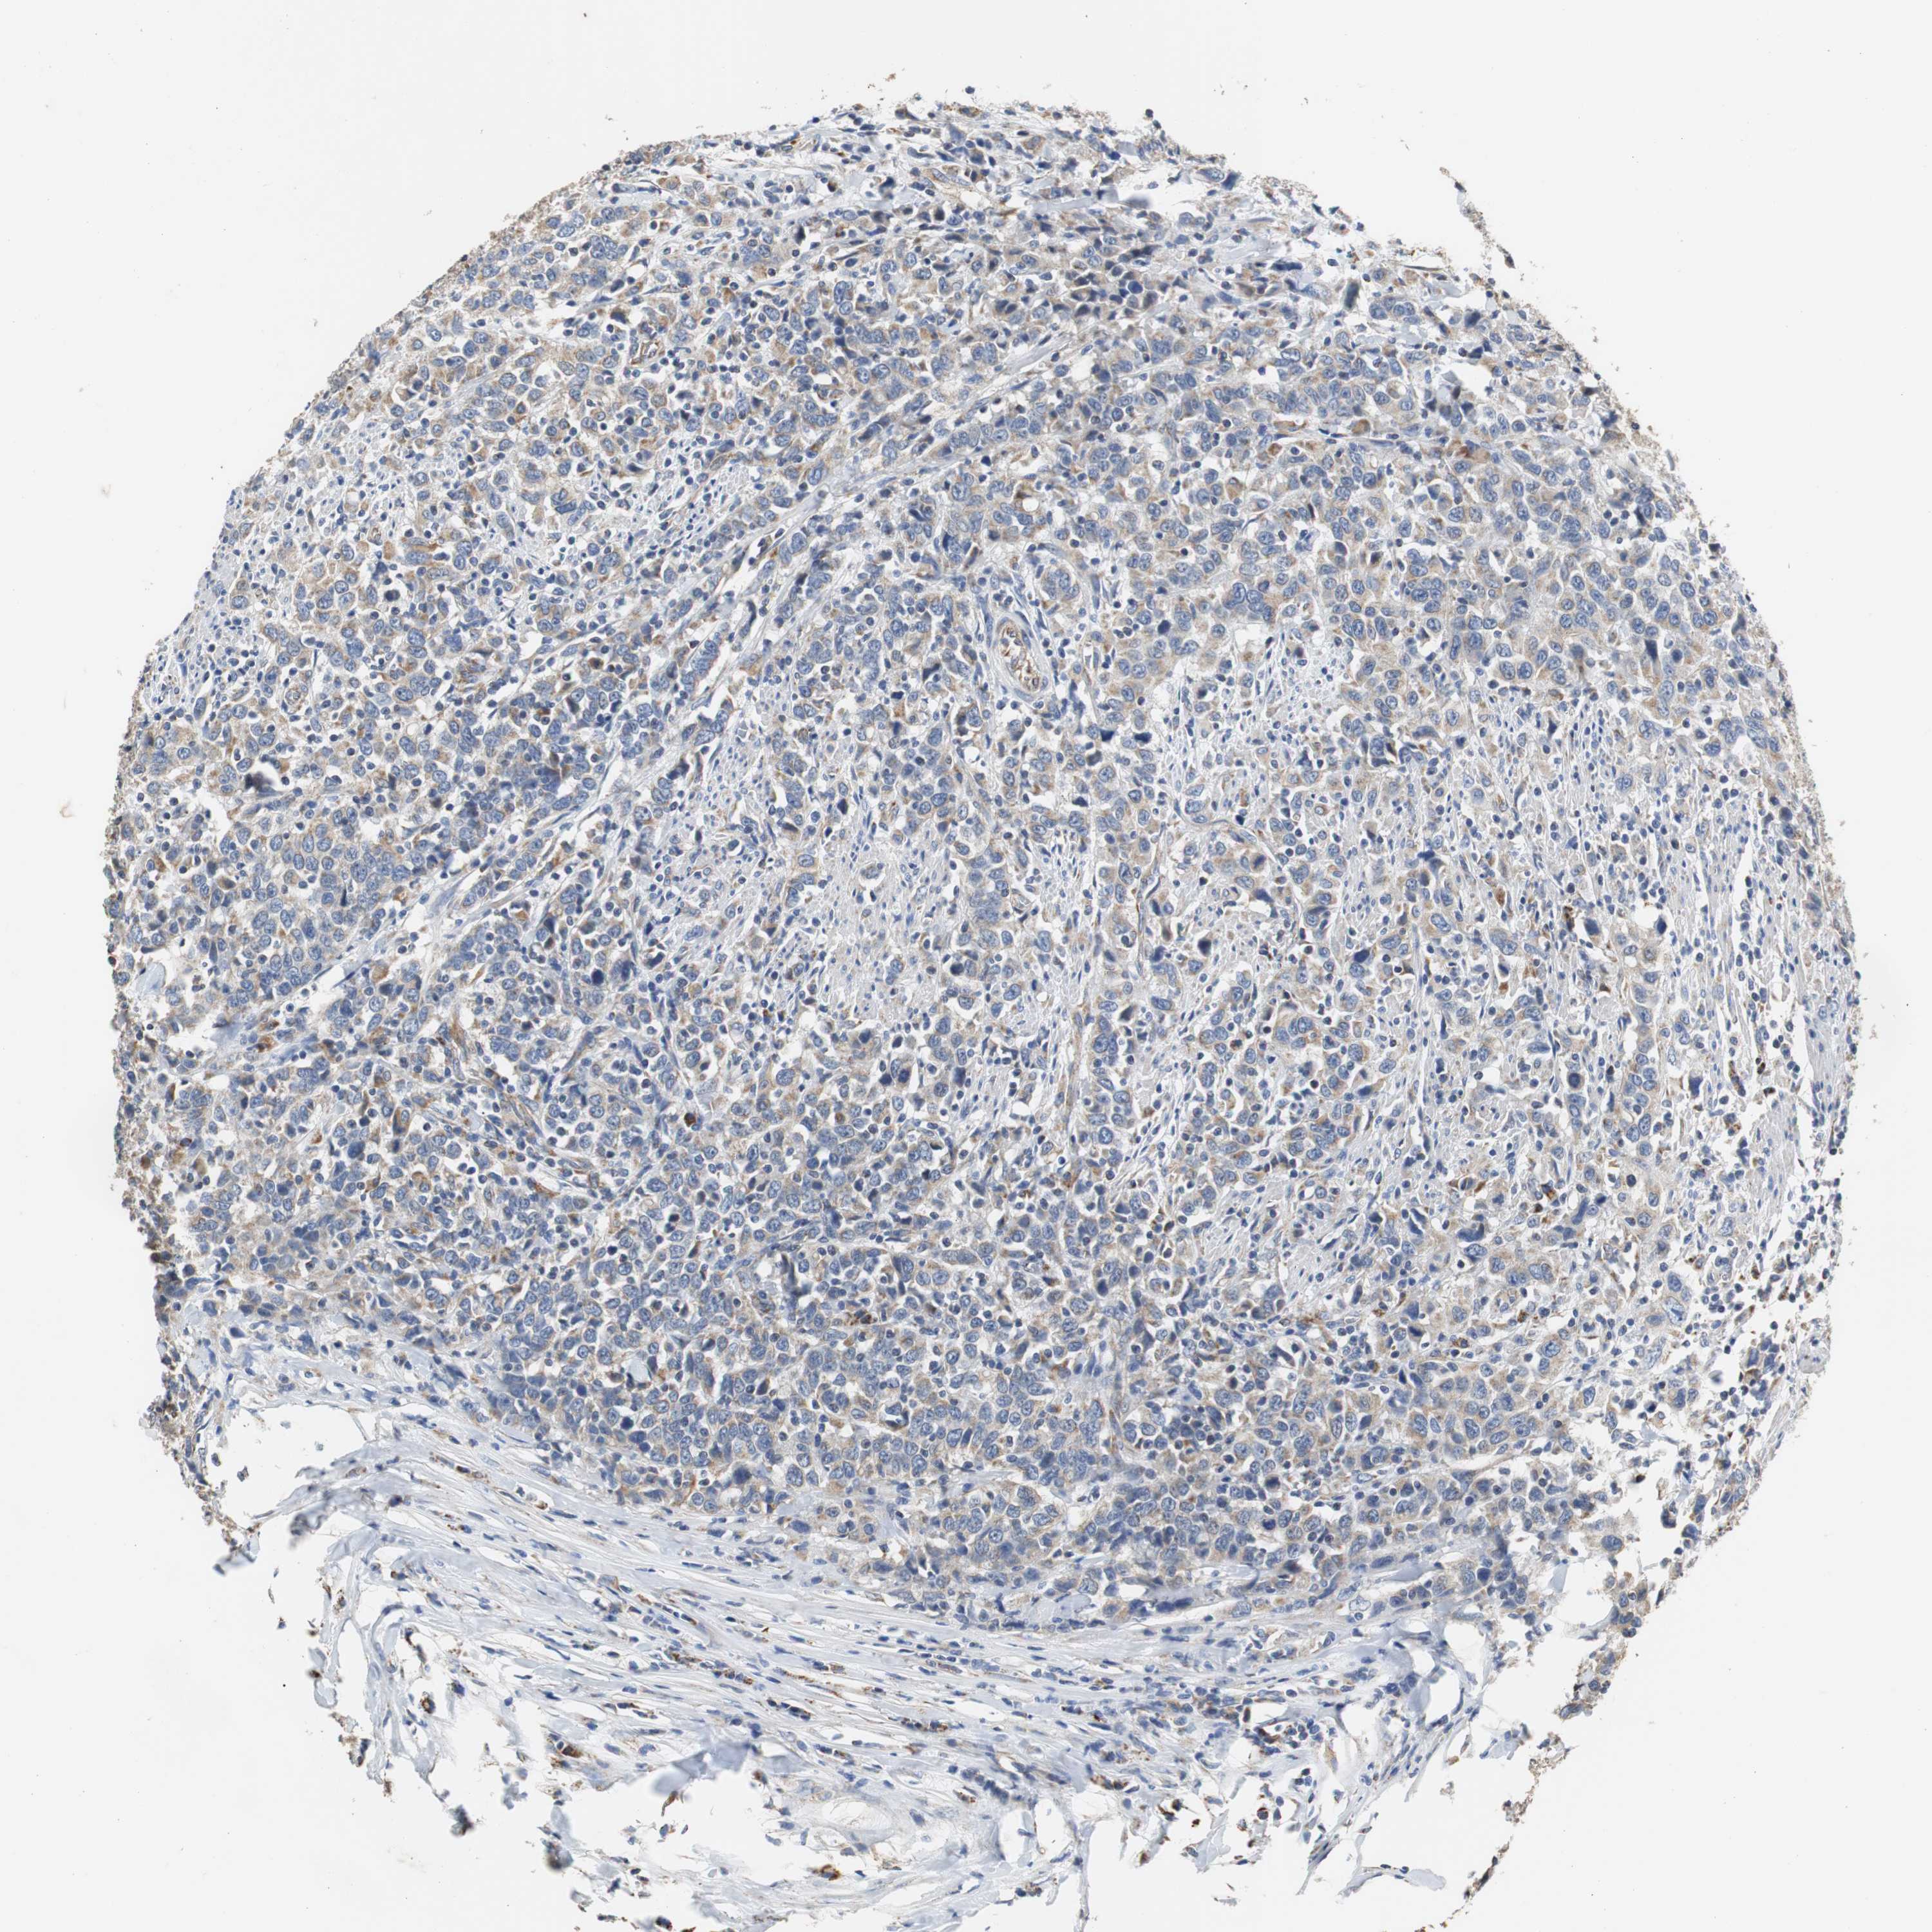

UROTHELIAL CANCER - Protein expressioni

A mouse-over function shows sample information and annotation data. Click on an image to view it in a full screen mode. Samples can be filtered based on level of antibody staining by selecting one or several of the following categories: high, medium, low and not detected. The assay and annotation is described here.

Note that samples used for immunohistochemistry by the Human Protein Atlas do not correspond to samples in the TCGA dataset.

Antibody stainingi

Antibody staining in the annotated cell types in the current human tissue is reported as not detected, low, medium, or high, based on conventional immunohistochemistry profiling in selected tissues. This score is based on the combination of the staining intensity and fraction of stained cells.

Each image is clickable and will lead to virtual microscopy that enables deeper exploration of all samples and also displays staining intensity scores, fraction scores and subcellular localization as well as patient and tissue information for each sample.

Antibody HPA006277

Antibody HPA006507

Antibody CAB017027

Staining

High

Medium

Low

Not detected

Intensity

Strong

Moderate

Weak

Negative

Quantity

>75%

75%-25%

<25%

None

Location

Nuclear

Cytoplasmic/membranous

Cytoplasmic/membranous,nuclear

Urothelial carcinoma, Low grade

Urothelial carcinoma, High grade